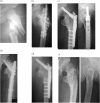

Infected non-union of subtrochanteric fractures is challenging to treat. We experienced two cases and had good clinical results. Treatment strategy comprised debridement without hesitation after considering later limb lengthening; insertion of the proximal lateral bone edge spike into the distal bone marrow cavity until achieving medial-side bony contact and holding good alignment to compensate for the medial-side bone loss, according to the modified Dimon method; and internal fixation with an angled plate in the decubitus position. The angle of the angled plate should be directed toward the abundant cancellous bone using preoperative computed tomography. Residual limb shortening after ORIF was improved by limb lengthening.